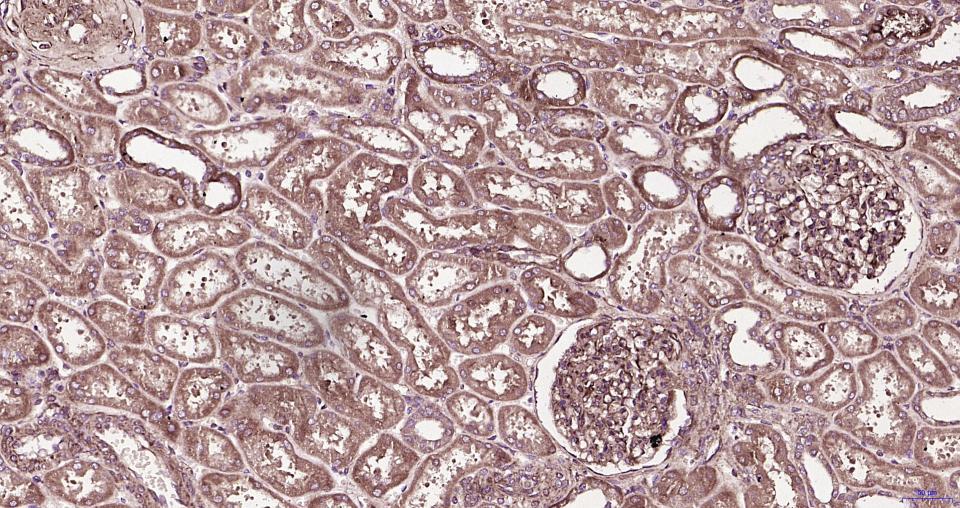

Paraformaldehyde-fixed, paraffin embedded Human kidney; Antigen retrieval by boiling in sodium citrate buffer (pH6.0) for 15 min; Antibody incubation with RhoA/B/C Monoclonal Antibody, Unconjugated (bsm-61200R) at 1:200 overnight at 4°C, followed by conjugation to the bs-0295G-HRP and DAB (C-0010) staining.

Paraformaldehyde-fixed, paraffin embedded Mouse kidney; Antigen retrieval by boiling in sodium citrate buffer (pH6.0) for 15 min; Antibody incubation with RhoA/B/C Monoclonal Antibody, Unconjugated (bsm-61200R) at 1:200 overnight at 4°C, followed by conjugation to the bs-0295G-HRP and DAB (C-0010) staining.

Paraformaldehyde-fixed, paraffin embedded Rat kidney; Antigen retrieval by boiling in sodium citrate buffer (pH6.0) for 15 min; Antibody incubation with RhoA/B/C Monoclonal Antibody, Unconjugated (bsm-61200R) at 1:200 overnight at 4°C, followed by conjugation to the bs-0295G-HRP and DAB (C-0010) staining.